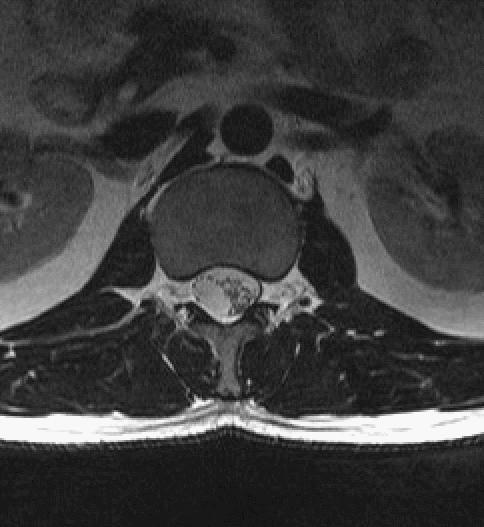

MRI

T1WI矢状位,定位图中所示最下一节为腰5椎体。T2WI、T2WI压脂、T2WI轴位、T1WI增强

A 椎管内2个富血供结节

B 椎管内病灶位于硬膜外

手术经过:开窗后见硬膜囊内压力较高,以尖刀切开硬膜,见T12-L1椎体水平椎管内有2枚肿物,分离肿物远近端,分别各有一束神经与肿物无法分离,切断神经;将2枚肿物完整切除。